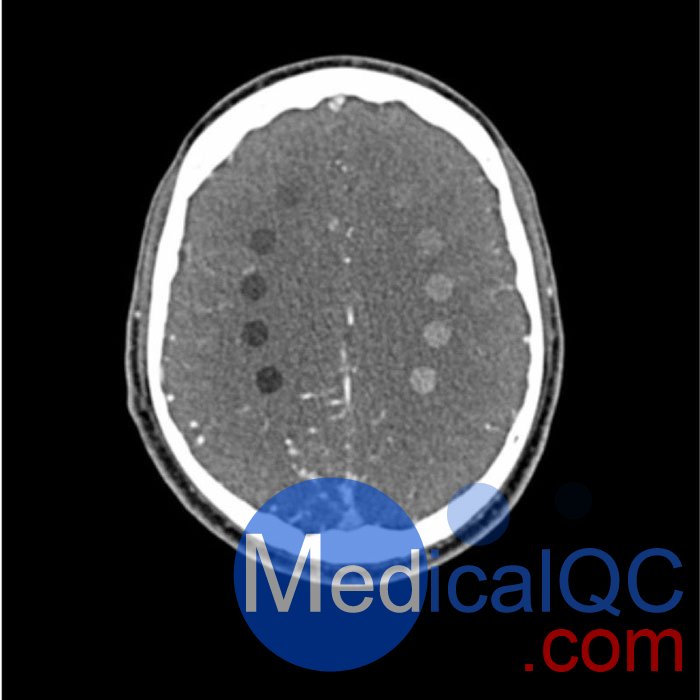

該模型在半卵圓中心有 10 個低對比度病變,右半球有動靜脈畸形。

在腦室周圍和室上水平的半卵圓中央每側各有 5 個桿狀病變。

病變直徑: 10 mm

病變高度: 10.5 mm

病變對比度:120 kVp 時約為 -60 至 -20 和 20 至 60HU

WEK-5005腦血管造影頭模,WEK-5005頭模, CTA AVM頭模成像效果圖:

WEK-5005腦血管造影頭模,WEK-5005頭模, CTA AVM頭模成像效果圖